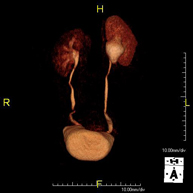

Prueba diagnóstica no invasiva que consiste en el estudio de las arterias renales, obteniendo imágenes de alta definición anatómica mediante el empleo de un campo electromagnético y ondas de radio (con un emisor y un receptor). Es indispensable el uso de contraste paramagnético (Gadolinio). Sin embargo, no utiliza radiación ionizante. La calidad de las imágenes permite realizar reconstrucciones en 2D y 3D. Esta prueba está indicada por ejemplo en aquellos pacientes que sufren de HTA refractaria al tratamiento, en pacientes con lesiones renales para tener un mapa "vascular" pre-quirúrgico, etc. - Entero-RM

Prueba diagnóstica no invasiva que consiste en el estudio de la arteria aorta abdominal, obteniendo imágenes de alta definición anatómica mediante el empleo de un campo electromagnético y ondas de radio (con un emisor y un receptor). Es indispensable el uso de contraste intravenoso paramagnético (gadolinio). Sin embargo, no utiliza radiación ionizante. La calidad de las imágenes permite realizar reconstrucciones en 2D y 3D. Esta prueba está especialmente indicada como estudio pre-quirúrgico (mapa vascular) antes de intervenciones percutáneas o quirúrgicas de aorta abdominal, estudio complementario en pacientes con isquemia de miembros inferiores… - Angio-RM Arterias renales

Prueba diagnóstica no invasiva que consiste en el estudio de la arteria aorta abdominal, obteniendo imágenes de alta definición anatómica mediante el empleo de un campo electromagnético y ondas de radio (con un emisor y un receptor). Es indispensable el uso de contraste intravenoso paramagnético (gadolinio). Sin embargo, no utiliza radiación ionizante. La calidad de las imágenes permite realizar reconstrucciones en 2D y 3D. Esta prueba está indicada por ejemplo en aquellos pacientes que sufren de HTA refractaria al tratamiento, en pacientes con lesiones renales para tener un mapa "vascular" pre-quirúrgico… - Angio-RM Arterial extremidades inferiores